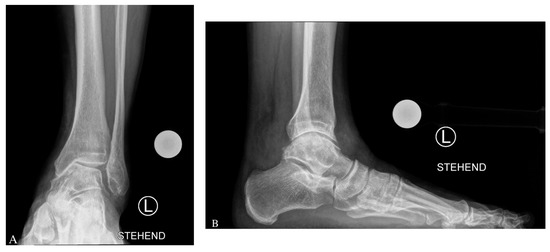

For lateral closing wedge osteotomy of the fibula and tibia, a lateral approach over the fibula is used [5]. The skin incision starts at the tip of the fibula to proximal over the distal third of the fibula. The fibula, the tibia, and the anterior syndesmosis are then exposed. To preserve ankle joint congruency with a lateral closing wedge osteotomy, shortening of the fibula is needed [5]. The fibula osteotomy is performed by a Z-shaped osteotomy at which the amount of fibula shortening is performed on both ends of the Z. The lateral part of the tibia is then prepared and protected by two Hohmann hooks, dorsal and anterior. Two K-wires are then placed in the tibia above the syndemosis in a converging way in accordance with the amount of correction that was preoperatively planned (MDTA angle) [27]. After that, the osteotomy is performed, and the gap is closed; the correction is stabilized with an angular stable plate. Finally, the position and length of the fibula is adjusted and secured with interfragmentary screws and a fibula plate [27]. See case example in Figure 2.

Figure 2.

Chronic Painful Posttraumatic Varus Ankle Osteoarthritis (OA) with Medial Degeneration of the Ankle Joint with Pes Planus Foot. In this case, there was preoperative a varus ankle OA with a hindfoot varus and a rare concomitant flatfoot at the midfoot (A–D). A complex reconstruction was performed (E–H): Supramalleolar lateral closing wedge osteotomy of the tibia (Anatomical Anterolateral Tibial Plate Aptus, Medartis, Basel, Switzerland), fibular shortening osteotomy (Anatomical Fibular Aptus Plate, Medartis, Basel, Switzerland), anteromedial osteophytes removal/cheilectomy, lateral ankle ligament repair, and Deltoid release. Note that a midfoot Cotton osteotomy (Cotton-Plate with Titanium Wedge, Medartis, Basel, Switzerland) was performed in order to counteract the pre-existing flatfoot deformity.